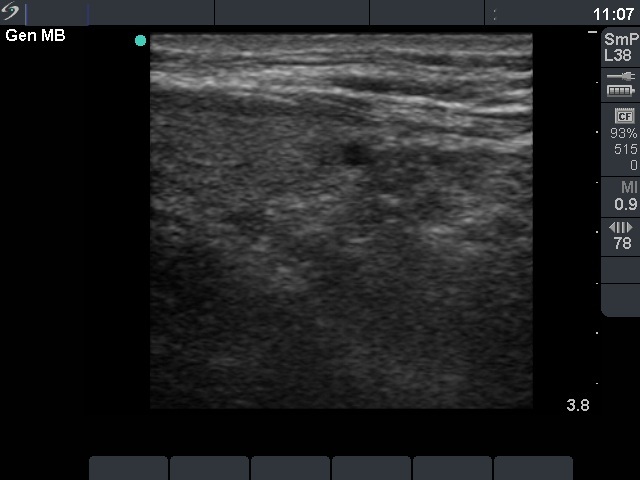

Ethanol sclerotherapy: parathyroid lesions - Case 2

Six months after the therapy (ultrasonographic picture 2)

Under the left lobe.